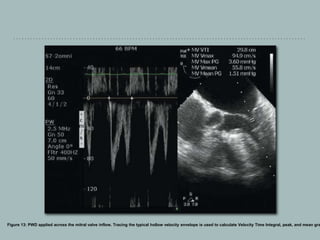

The velocity is displayed as a spectral waveform on the vertical axis with time

displayed on the horizontal axis .

By convention, blood flowing towards the probe is displayed above the baseline and

blood flowing away from the probe is displayed below the baseline. The baseline

should be adjusted to accommodate the complete waveform.

Figure 13: PWD applied across the mitral valve inflow. Tracing the typical hollow velocity envelope is used to calculate Velocity Time Integral, peak, and mean gra

Pulse wave Doppler PWDmeasures low-velocity flows at a specific point along the beam axis. The beam axis should be parallel to the blood flow to maintain accuracy. For practical purposes, if the angle between the US beam and the blood flow is greater than 20°, there is an unacceptable degree of error in estimating the velocity. PWD is used to diagnose diastolic dysfunction from mitral valve and pulmonary vein inflow patterns, estimate aortic valve area and calculate stroke volume. [27] Sampling PWD uses a single piezoelectric crystal which acts both as a transmitter and receiver to measure blood velocity intermittently at a particular area called as sample volume. Adjusting the gate control can increase or decrease the size of the sample volume. The trackball is used to place the sample volume at the area of interest.

• 91.

Depth The ROI shouldbe as near the transducer as possible. This is because as imaging depth increases, there is a decrease in the pulse repetition frequency. Gain Gain is used to amplify the returning Doppler signals. The audio volume can be used to hear the Doppler shift to optimize the spectral waveform. Display The velocity is displayed as a spectral waveform on the vertical axis with time displayed on the horizontal axis . By convention, blood flowing towards the probe is displayed above the baseline and blood flowing away from the probe is displayed below the baseline. The baseline should be adjusted to accommodate the complete waveform.

• 92.

Figure 13: PWDapplied across the mitral valve inflow. Tracing the typical hollow velocity envelope is used to calculate Velocity Time Integral, peak, and mean gra